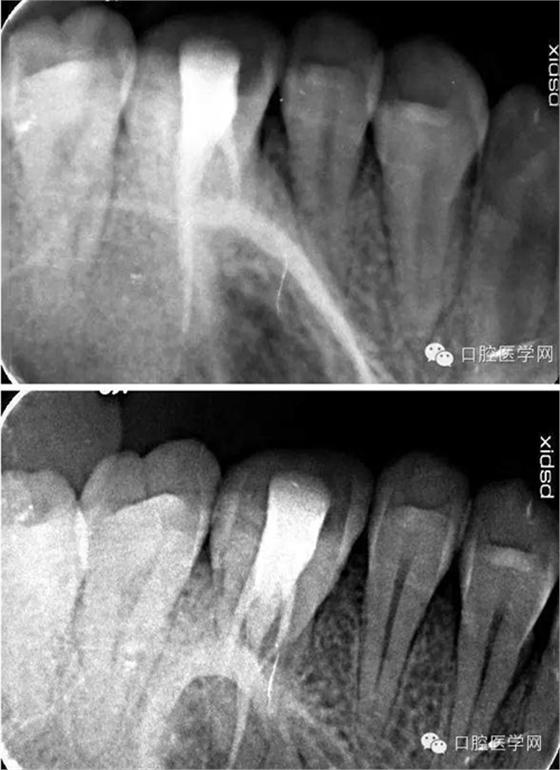

26根尖片可見低密度暗影:

二次復(fù)診患者訴36疼,根尖片未見異常。

術(shù)中試尖x線片:

術(shù)后x線片: